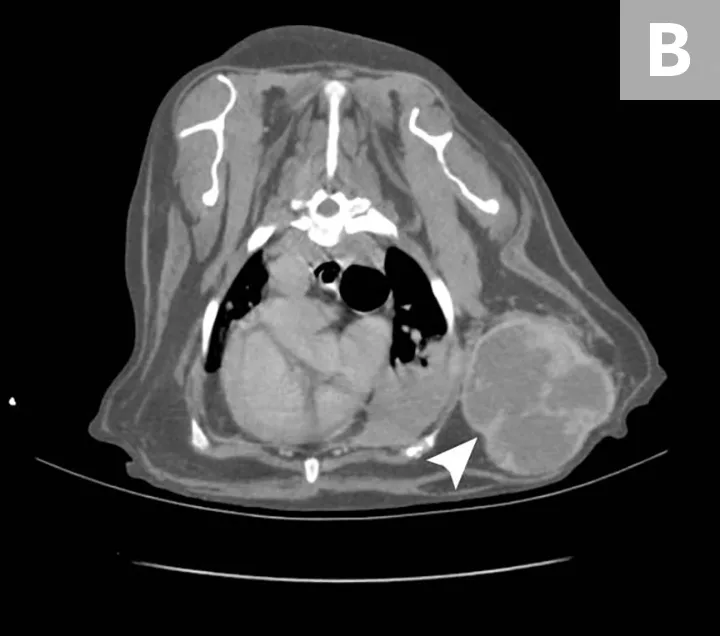

HSA can develop in any vascular organ or tissue but is most commonly found in the spleen (≈50%), right atrium and/or auricle (≈25%), and skin or SC tissue (≈15%; Figure 1).4 Most dogs diagnosed with HSA are geriatric, with a predisposition observed in German shepherd dogs, golden retrievers, and Labrador retrievers.5-7 Splenic HSA is a common splenic malignancy and is accompanied by life-threatening complications (ie, hemoabdomen and distant metastases).8-11 The mode of metastatic spread varies for patients with HSA that involves the abdominal visceral organs (eg, spleen, liver, kidneys). Regional dissemination of disease in the abdominal cavity or retroperitoneal space is enabled by the local deposition of tumor cells following primary tumor rupture, but distant metastasis requires hematogenous circulation, vascular entrapment, and successful colonization of detached tumor cells. Common metastatic sites include the liver, omentum, mesentery, and lungs.7,12 HSA also tends to metastasize to the CNS.13,14

Primary noncutaneous HSA involving the head of the spleen (A) and the right auricle (B, arrowheads). Images courtesy of Laura Garrett, DVM, DACVIM (Oncology), and Louis-Philippe de Lorimier, DVM, DACVIM (Oncology)